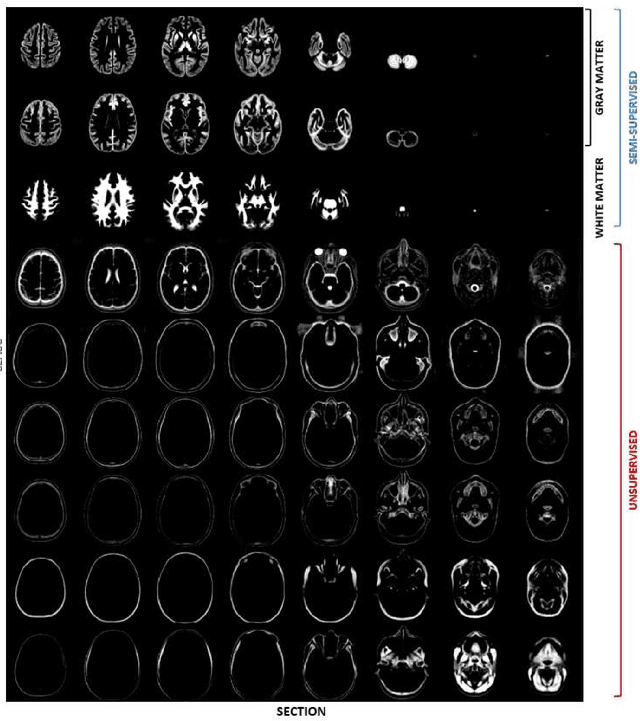

In this paper we will focus on the potential and on the challenges associated with the development of an integrated brain and spinal cord modelling framework for processing MR neuroimaging data. The aim of the work is to explore how a hierarchical generative model of imaging data, which captures simultaneously the distribution of signal intensities and the variability of anatomical shapes across a large population of subjects, can serve to quantitatively investigate, in vivo, the morphology of the central nervous system (CNS). In fact, the generality of the proposed Bayesian approach, which extends the hierarchical structure of the segmentation method implemented in the SPM software, allows processing simultaneously information relative to different compartments of the CNS, namely the brain and the spinal cord, without having to resort to organ specific solutions (e.g. tools optimised only for the brain, or only for the spinal cord), which are inevitably harder to integrate and generalise.